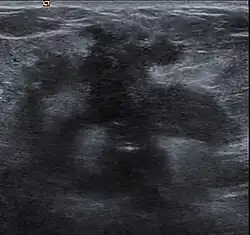

Desmoplastic reaction to breast cancer

Desmoplasia refers to growth of dense connective tissue or stroma.[2] This growth is characterized by low cellularity with hyalinized or sclerotic stroma and disorganized blood vessel infiltration.[3] This growth is called a desmoplastic response and occurs as result of injury or neoplasia.[2] This response is coupled with malignancy in non-cutaneous neoplasias, and with benign or malignant tumors if associated with cutaneous pathologies.[3]